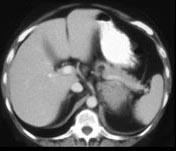

问题 女,47岁,满月脸、向心性肥胖伴高血压1月,请结合所提供图像,作出诊断 ( )

选项 A、左肾上腺嗜铬细胞瘤 B、左肾上腺增生 C、左肾上腺腺癌 D、左肾上腺转移瘤 E、左肾上腺腺瘤

答案 C